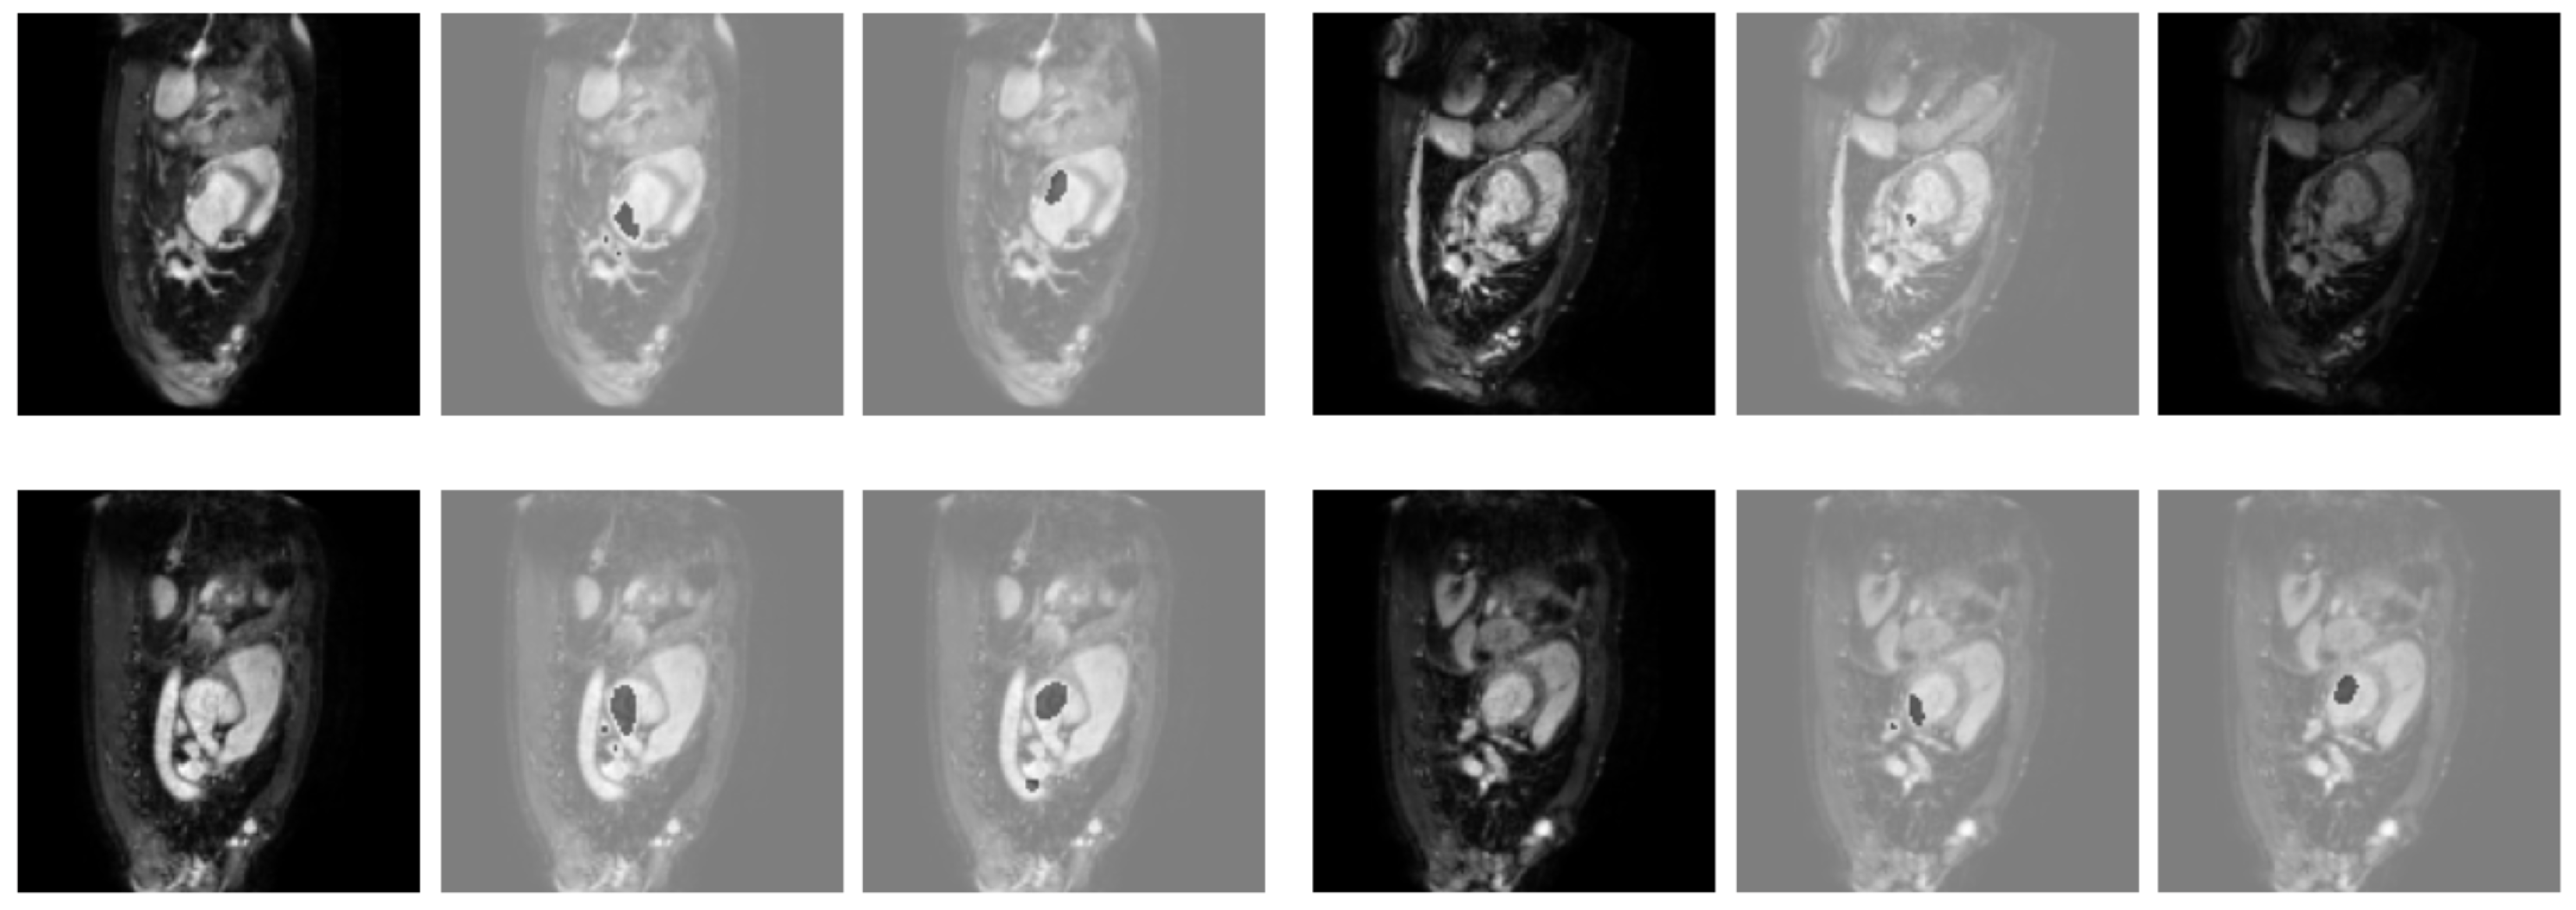

3.2. Results Obtained on the Heart MRI Dataset

| Dice | TPR | TNR | HD95 | |

|---|---|---|---|---|

| U-Net | 73.94% | 80.71% | 98.24% | 24.28 |

| UNet++ | 74.06% | 90.25% | 97.50% | 28.33 |

| Att-UNet | 72.82% | 83.74% | 97.84% | 27.39 |

| Focus-UNet | 68.03% | 87.79% | 96.72% | 39.92 |

| SAB-Net | 78.27% | 82.63% | 98.67% | 21.21 |